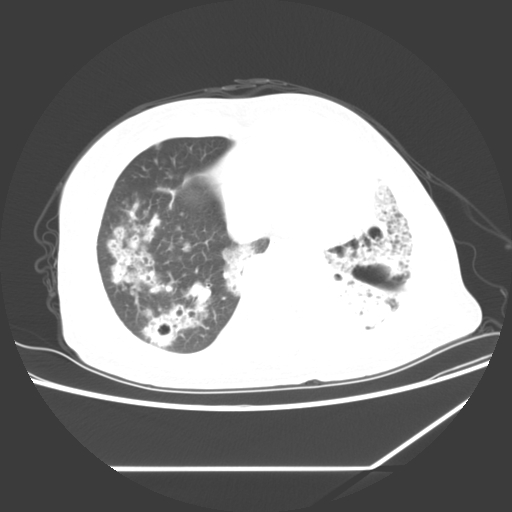

标题: CT25393:病人45岁,咳嗽,吐黄痰带血丝,发热,胸闷月余 [打印本页]

标题: CT25393:病人45岁,咳嗽,吐黄痰带血丝,发热,胸闷月余

1、左肺中央型肺癌并双肺弥漫性转移   2、双肺部感染    3、肺大泡     4、左侧胸腔积液

双侧肺弥漫性病变,可见“空泡征”及“蜂窝征”,考虑肺泡癌可能性大,左侧胸腔积液,考虑胸膜受累可能!

1)不排除肺泡癌可能。2)左侧胸腔积液。